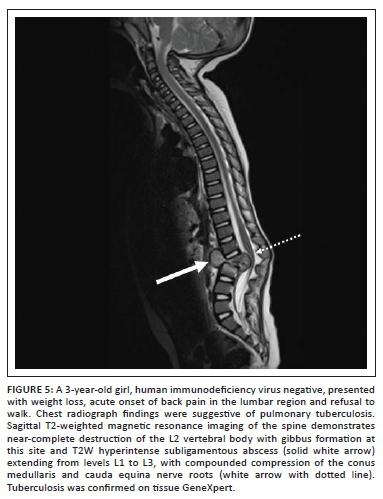

Subsequent spread of infection is beneath the anterior or posterior longitudinal ligament or through the vertebral end plates (Figure 4).6,8 Paraspinal and extradural soft tissue and gibbus formation are the most common findings reported. On MRI, the paraspinal or subligamentous abscesses demonstrate T2-weighted (T2W) hyperintense and T1W hypointense signal.6,8

Extradural abscess may cause cord compression with neurological fallout (Figure 5).6,8 Psoas abscess formation with possible associated calcifications is often a clue to the diagnosis.6,8